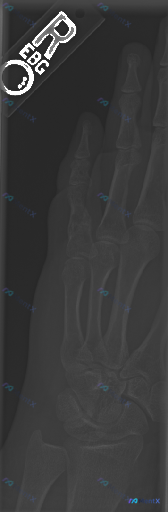

看到一份右手斜位X光片的读片资料,先把影像部分放出来:

影像所见(摘要):

- 掌骨、指骨、腕骨形态完整,骨皮质连续,未见明确骨折线、骨膜反应或骨质破坏

- 腕掌、掌指、指间关节对位正常,关节面光滑,间隙未见明显狭窄/增宽

- 骨密度均匀,软组织轮廓正常,未见明显肿胀或高密度异物

影像结论:

在当前投照体位和影像质量下,未见明显的骨折、脱位或显著的病理性骨质破坏征象。